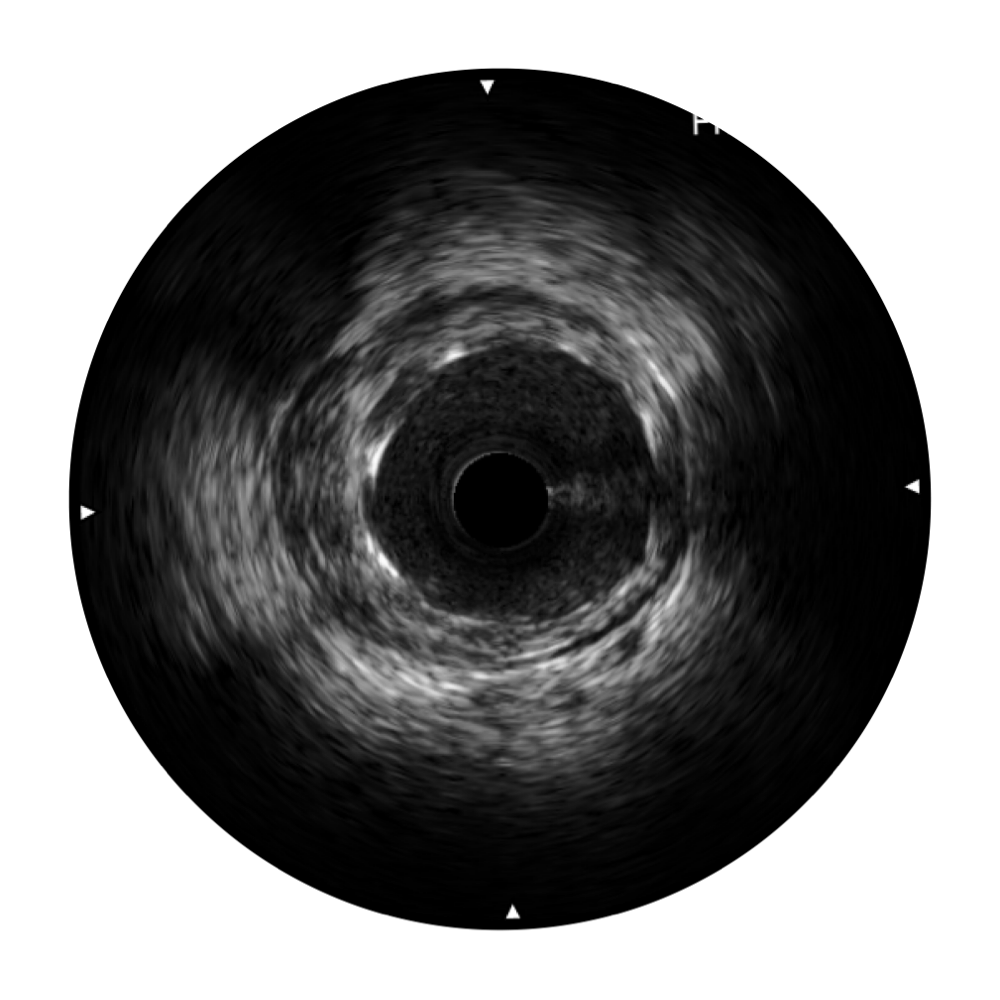

球速体育入口宽频IVUS图像

对比传统IVUS导管成像,球速体育入口宽频IVUS图像的近场支架梁显影更细腻,远场中膜外血管仍清晰可辨,兼顾远中近,兼顾分辨力与穿透深度